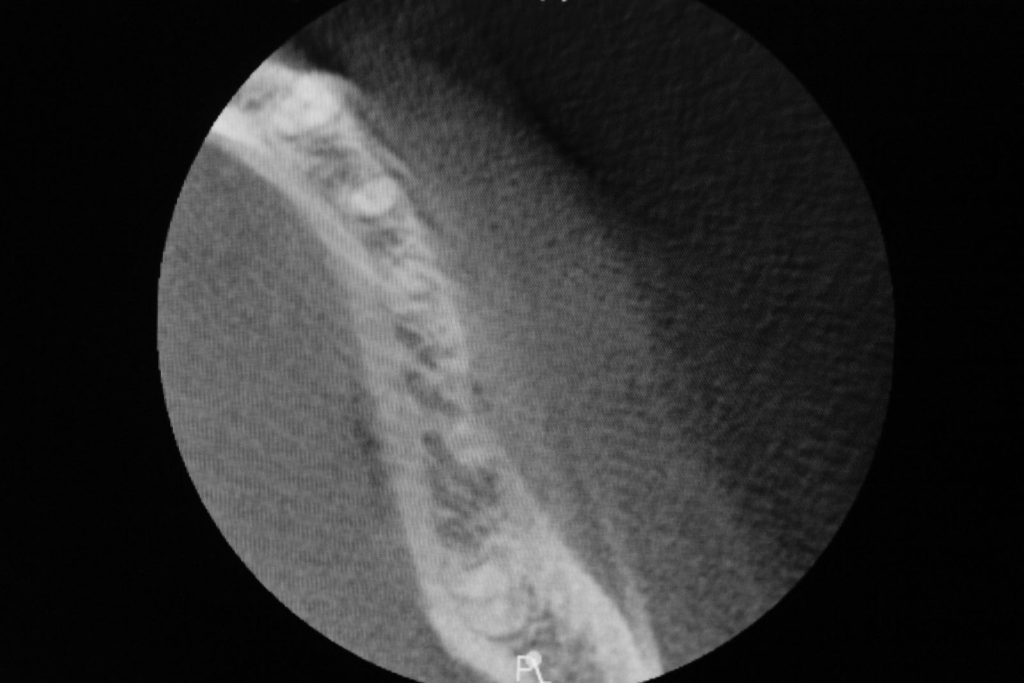

Przed podjęciem leczenia należy określić stopień zaniku kości szczęk oraz żuchwy. W tym celu przeprowadza się badanie kliniczne oraz odpowiednią diagnostykę obrazową pacjenta. Uwzględnia ona zdjęcie panoramiczne OPG jako podstawę dwuwymiarowego obrazowania podłoża kostnego oraz możliwe jest badanie tomograficzne CT lub bardziej precyzyjna tomografia stożkowa CBCT. Opcjonalnie wykorzystywana diagnostycznie tomografia pozwala na bardziej wnikliwą ocenę stopnia zaniku kości w trójwymiarowym, przestrzennym obrazie.

Zatoki szczękowe to symetrycznie umieszczone w kościach szczęk przestrzenie powietrzne, posiadające komunikację z jamą nosa. Średnio pojemność zatok wynosi 24 cm3, a ściany wyścielone są błoną śluzową (membrana Schneidera). Dno zatoki szczękowej stanowi wyrostek zębodołowy, w którym umieszczone są zęby, często zlokalizowane tuż pod cienką wyściółką zatoki. Statystycznie najwęższy obszar kostny w tej strefie zlokalizowany jest na wysokości zębodołów pierwszego i drugiego zęba trzonowego.